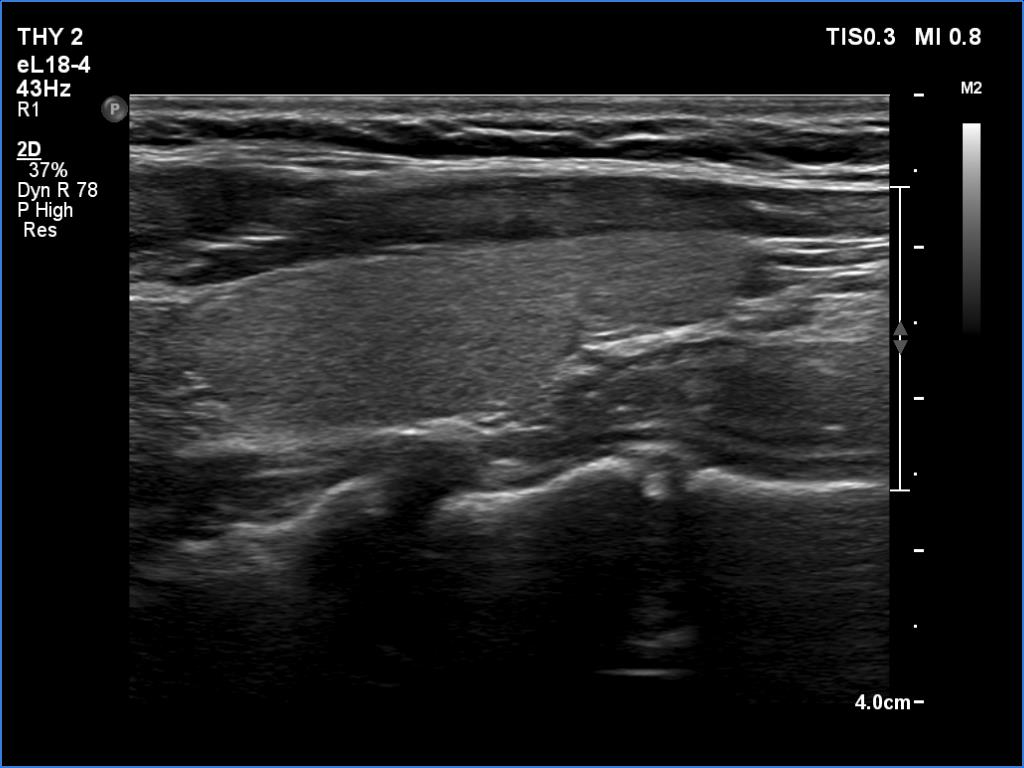

Ultrasonography. The thyroid was echonormal. There were no discrete lesions. The vascularity was average or slightly decreased. Microflow imaging has not revealed increased number of intrathyroidal vessels.